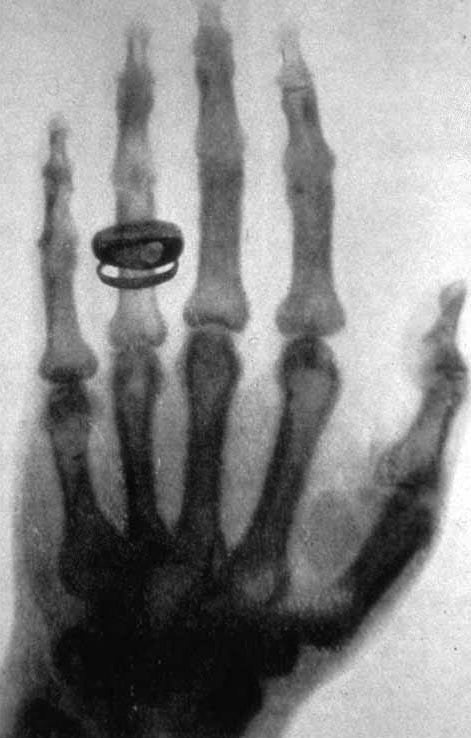

La primera radiografía de la historia (Wikimedia Commons)

El fenómeno de los rayos X estalló en Londres y otras ciudades británicas en 1896. Miles de personas acudieron a exposiciones públicas, donde observaron sus propias manos convertidas en esqueletos visibles, con anillos resaltando sobre los huesos. Ingenieros presentaron estos avances tras el hallazgo de Wilhelm Röntgen durante el año anterior en Alemania, lo que permitió ver el interior de objetos en tiempo real y reveló una nueva dimensión científica. La novedad se instaló en el centro del debate social y mediático durante ese año, y la noticia movilizó tanto al público general como a la comunidad médica.